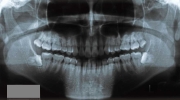

初診時